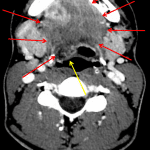

- Complex fluid collection extending along the right floor of the mouth and submandibular space

- Periapical lucency involving the right second mandibular molar with cortical breakthrough medially

- Reactive enlargement of right greater than left cervical lymph nodes

- Ludwig angina

Abscess extending along the right floor of the mouth and right submandibular space with extensive surrounding edema, concerning for Ludwig angina, likely of odontogenic origin given periapical lucency in the second right mandibular molar with cortical breakthrough. Floor of the mouth edema exerts mass effect on the tongue and narrows the oropharynx posteriorly, which remains patent. Urgent ENT consultation is recommended.